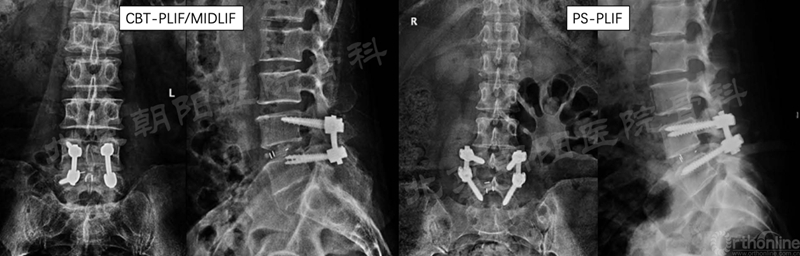

本团队(首都医科大学附属北京朝阳医院)通过前瞻性队列研究对比了CBT技术和PS技术在腰椎融合中的应用,相关研究发表在Clinical Interventions in Aging和BMC Musculoskeletal Disorders杂志,主要研究结论如下:

1. CBT组患者术后3个月ODI和JOA评分显著高于PS组;

2. 对于骨质疏松患者,CBT组患者术后螺钉松动率显著低于PS组;

3. 在早期随访中,CBT组比PS组患者的影像学ASD发生率更低;

4. 在12月随访中,通过CT显示,两组患者融合率无明显差异;

5. 两组患者在腰椎矢状面序列的恢复方面无显著差异。